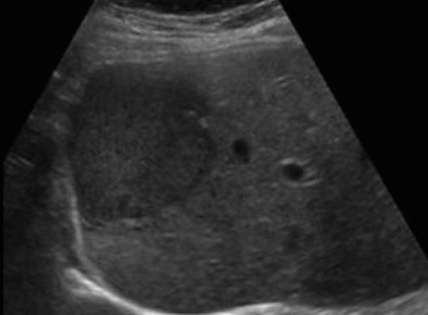

hepatocellular adenoma (간세포선종) US finding

- 원형의 저에코, 등에코, 고에코등의 종괴로 다양하다.

- 피막을 갖는다

- 크기가 8~14cm으로 크다

- hypoechoic rim (띠가 혈관이다)

- usually solitary and heterogeneous